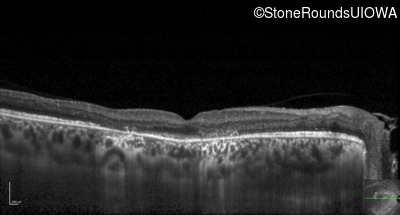

Optical Coherence Tomography - Right - 5/200

Exemplar / OCT Stack

OCT Stack

Optical Coherence Tomography - Left - 20/25 -1